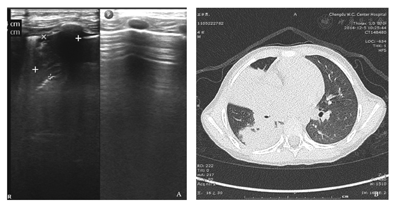

A.肺部超声可见胸膜线增厚、模糊,左肺内斑片状弱回声区,右前肺内肝样实变区,可见B-线,右侧胸腔少量积液;B.CT可见右肺广泛炎症,伴右肺门及纵隔淋巴结稍肿大,右侧少量胸腔积液。

肺实变是CAP中重要的超声影像学特点,也是CAP诊断中容易识别的LUS征象,一旦发现有实变征象,再结合临床表现则具有确诊的意义。本研究中80例(46.2%)CAP患儿均见不同程度的肺实变;与之相伴的支气管征是在肺实变中常见到的一种超声图像特征,表现有支气管充气征、支气管充液征,在实时超声下可以见到支气管充气/充液征可以是动态的或是固态的,可以用以鉴别肺实变和合并肺不张[10]。肺不张的超声表现主要有病变区肺实变伴肺搏动、肺滑动征消失及平行排列的支气管充气征等[11,12],而动态空气支气管征的存在排除阻塞性肺不张[13]。LUS中发现大量胸腔积液的存在则提示压迫性肺不张[7];同时,利用积液的不同特点可以辅助判断其性质,如漏出液表现为无回声征象;渗出液可以是无回声,或低回声,或包含各种有回声的物质(浮游生物征),或有分隔[14](图4)。